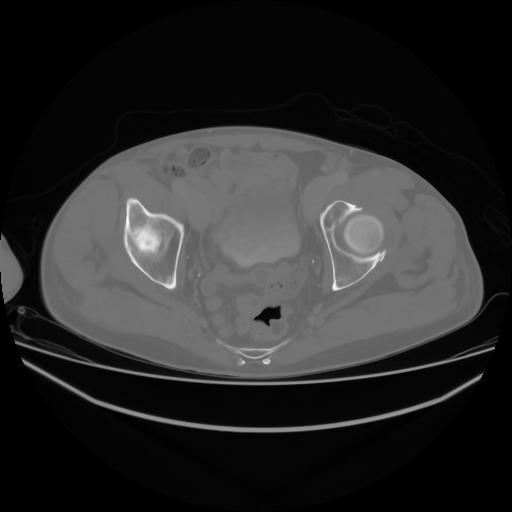

4 CUERPO,CE,Axial,3.0,CUERPO,,